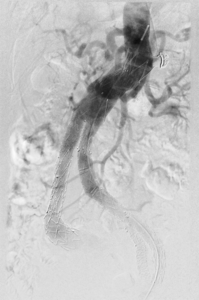

Behandlung des undichten Stentes in der Hauptschlagader:

Nach der Versorgung einer Erweiterung der Hauptschlagader des Bauches kann es zu Undichtheiten des Stentes oder zu einem Zufluss aus kleinen Arterien kommen, die zu einer gefährlichen Zunahme der Erweiterung führen können. Für die Behandlung stehen uns alle Behandlungsmethoden zum Verschließen zur Verfügung.